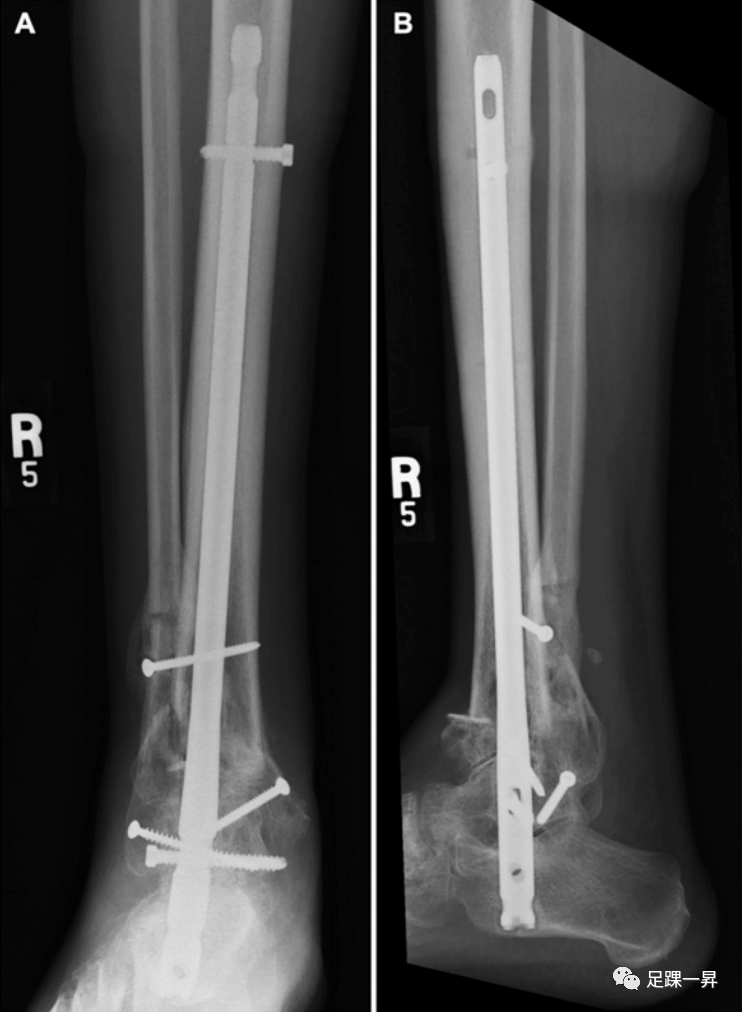

后足TTC髓内钉钉固定术也是下肢严重创伤后关节融合术的一个可行选择。在破坏性后足创伤性损伤中,它可能比更传统的关节融合术结构具有潜在的优势。理论上的好处包括微创插入和减少伤口并发症的可能性;缺点是距下运动的固有限制。多发性创伤和严重胫骨平台损伤的患者可能受益于放置后足髓内钉作为负荷分担装置,允许早期活动。低需求的患者合并疾病,如糖尿病和血管病,是这种微创稳定技术的理想候选人,以限制伤口愈合受损引起感染并发症的风险。

△图示一例开放性Pilon骨折,伴有严重的不可逆软骨损伤。最终治疗采用急性关节融合术,使用胫距跟钉结合腓骨植骨融合。